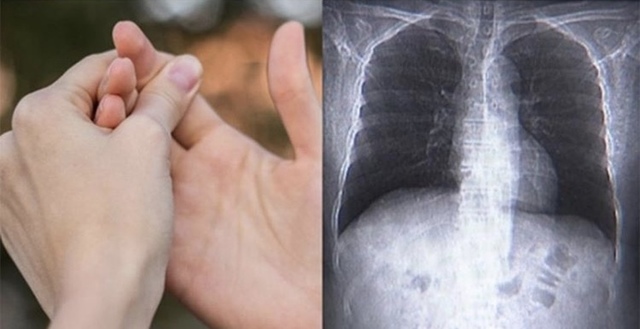

🤚'손가락' 으로 폐암 가능성 예측 테스트!

아무런 도구 없이 손가락만으로 폐암 가능성을 예측할 수 있는 테스트가 알려져 온라인 상에서 화제가 되고 있습니다.샴로트의 창문 테스트의 정확한 원리는 밝혀지지 않았지만 영국 암 연구소는 악성종양이 손가락에 액체가 쌓이는 호르몬을 생성할 수 있기 때문이라고 추정했습니다.실제로 해당 손가락테스트는 의료 전문가들이 환자의 상태를 확인하는 방법으로 사용되며 여러가지 질병의 징후가 될 수 있다고 합니다.손가락에 다이아몬드를 확인해보세요!